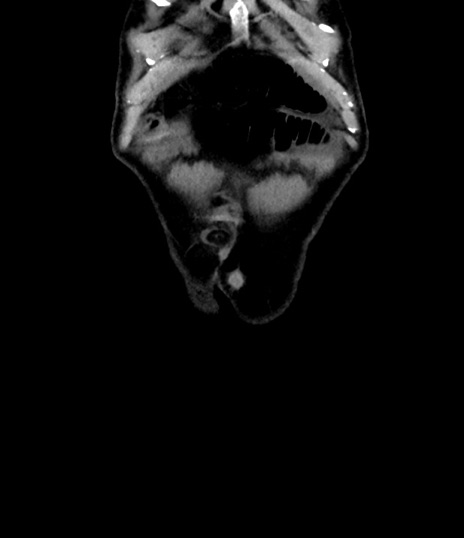

症例8(冠状断像)

【症例】 60歳代男性

【主訴】 黒色吐物

【現病歴】 4日前から嘔気自覚、2日前の朝食後にも嘔気あり、自分で手で嘔吐反射起こし嘔吐したところ血が混ざっていたため受診。

【既往歴】 5年前汎発性腹膜炎を伴う急性虫垂炎で手術、高血圧、前立腺肥大症、高脂血症

【身体所見】 腹部正中に手術癩痕あり 腹部平坦・軟圧痛なし膨満感あり

【データ】WBC 8400、CRP 4.54